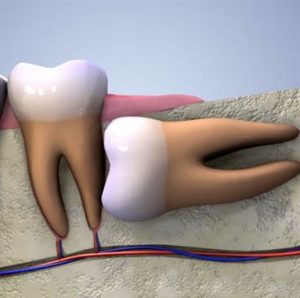

20 yaş dişi çekimi, çene yapısına tam uyum sağlayamayan, çürüyen, ağrıya veya enfeksiyona neden olan dişlerin cerrahi müdahaleyle alınması işlemidir. Bu işlem sonrası iyileşme sürecini hızlandırmak ve komplikasyonları önlemek için dikkat edilmesi gereken bazı önemli noktalar vardır. Peki, 20 yaş dişi çekimi sonrası nelere dikkat edilmelidir?